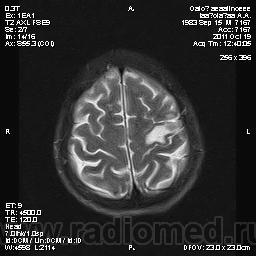

Молодой человек, жалуется только на головные боли и слабость в правой руке и ноге (около месяца).

Пациент полуасоциальный, нельзя исключить анамнез наркоманский....

ППН (включая ячейки пирамидок и сосцевидные отростки) тотально заполнены жидкостным компонентом...

Колеги, спасибо за высказывания. В данном случае про наркоманский анамнез указано не спроста... Есть мнение, что в этом лежит точка отсчета.... По поводу абсцесса и гематомы - не согласен; по поводу первого - нет соответствющей клиники, по поводу второго - не характерна локализация и сигнальные характеристики. Не буду томить общественность касательно собственного мнения. Есть две гипотезы, о которых думается в данном случае: прогрессирующая лейкоэнцефалопатия и новообразование... Но без контраста их не разрешить...